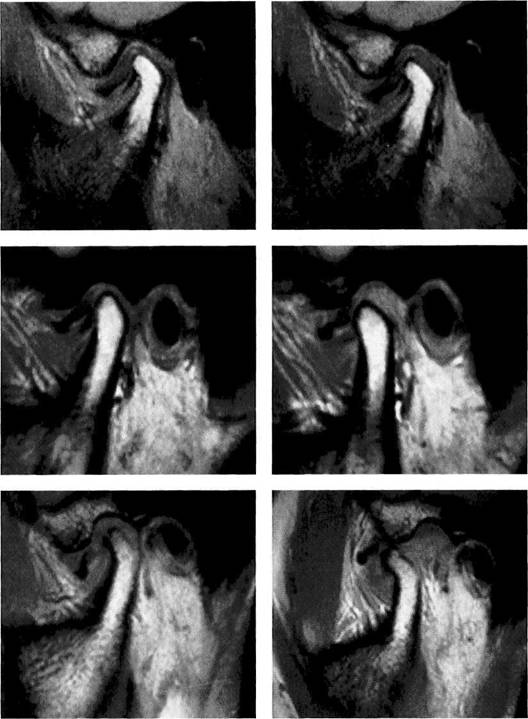

Habitual occlusion

MRI exposures at habitual occlusion are always made in a T1-weighting with the so-called spin-echo (SE) technique. The radiologist usually exposes six to eight slices, although images of only three layers (medial, central, and lateral) are necessary to adequately evaluate the disk-condyle relationship (Crowley et al. 1996). In a medial slice the lateral pterygoid muscle (arrows) can be identified. In the central slice (cen­ter) the posterior border of the as­cending ramus (arrows) is always visible.

Maximal jaw opening

The second obligatory joint series is made at maximal jaw opening in T2-weighting. The T2-weighting is well suited to reveal inflammatory reactions and joint effusions (Larheim 1995). The combination of exposures (Tl closed and T2 open) makes it possible to avoid a complete MRI series with both weightings. Again, a lateral, cen­tral, and medial slice are made. If the maximal jaw opening is not se­cure, false positive findings are like­ly to be made (Watt-Smith et al.

Therapeutic occlusion

The most important sequence of the MRI examination is the depic­tion of the positional relationships of the fossa, disk, and condyle in the treatment position of the mandible. The prognosis of a con­servative repositioning treatment depends to a large extent upon this view. To demonstrate a complete repositioning, medial, central, and lateral slices must again be made. When there is disk displacement without repositioning, this view is not as suitable as one in an angled coronal plane.